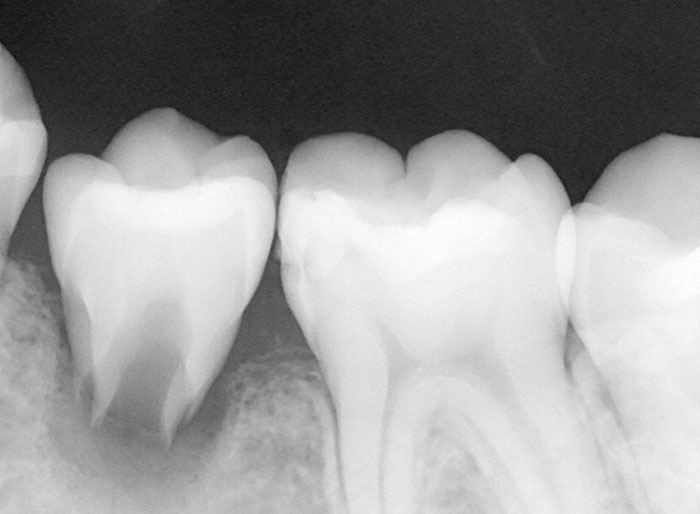

抜歯した親知らずを移植(2)

Before

After

左下の親知らずの歯を移植の症例です。